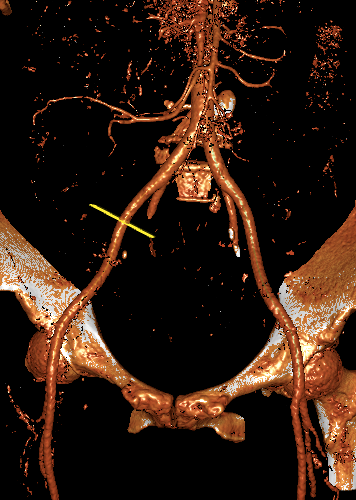

主动脉CT

主动脉瓣环平均直径:22.1mm;

左室流出道平均直径:23.7;

左冠脉开口:12.3mm;

右冠脉开口高度:11.2mm。

术前讨论:患者为三叶瓣主狭,左右冠瓣叶长,开口低,瓦氏窦小,左右冠高风险。

袁义强院长总结了该病例特点:三叶瓣,左右冠均高风险,解剖适合TAVR,年龄73岁,存在明确TAVR手术适应症。选择右股动脉入路,根据CT测量分析选择瓣膜大小,窦部情况可,瓣环平均直径22.1mm,计划22号球囊预扩,评估冠脉风险,选择植入24mm瓣膜。